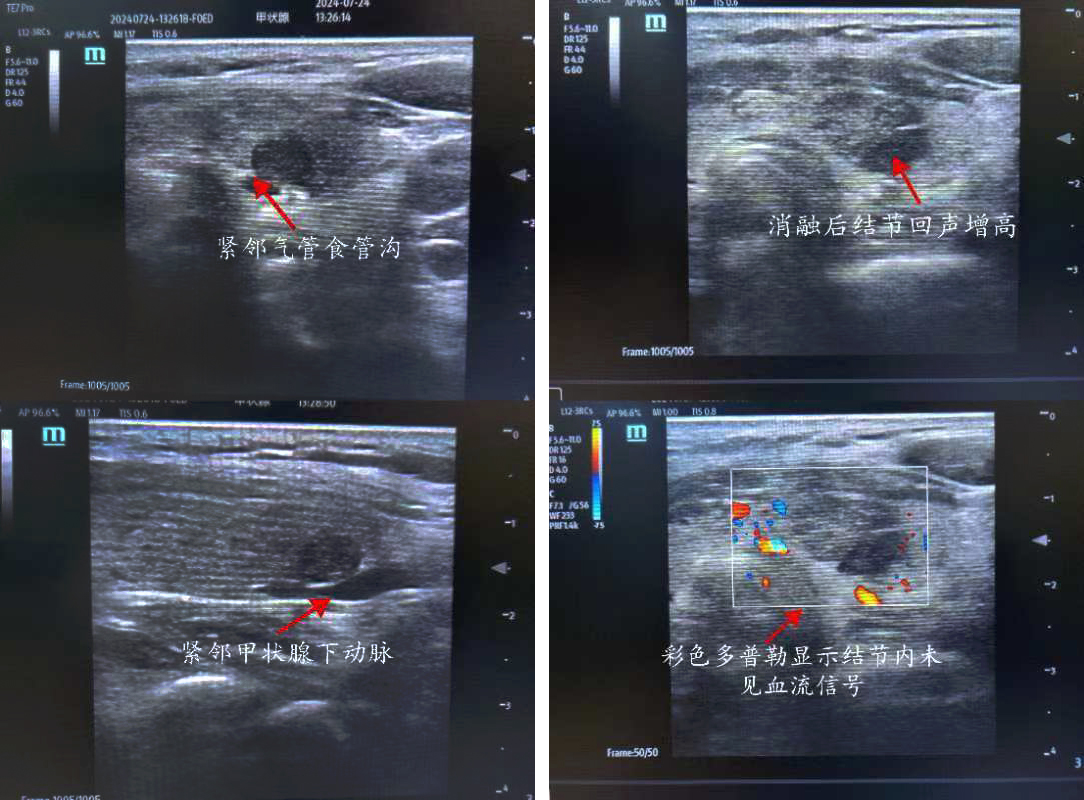

患者,女,50歲,甲狀腺彩超示:甲狀腺左側葉下極探及一約0.8*0.3cm低回聲結節,界尚清,形態不規則,內回聲不均質,內似可見點狀強回聲,周邊及其內可見血流信號 TI-RADS 4a級。入院后行甲狀腺左側葉結節細針穿刺細胞學檢查+BRAF基因檢測,結果示:考慮為濾泡上皮細胞非典型病變,BRAFV600E基因檢測未見突變。但患者左側葉4a結節位于腺體背側,緊鄰氣管食管溝,與左側喉返神經走行位置相近,患者自覺復查隨訪心理壓力大,強烈要求積極處理此結節。但因傳統手術切除治療創傷較大,美觀性較差,且術后可能需終身服藥,患者不愿接受手術切除。

俞景奎主任醫師、孫守毅副主任醫師及診療組詳細分析討論后,決定為患者行超聲引導下甲狀腺左葉結節微波消融術。對于該患者而言,行微波消融治療有兩大難點,一是患者左葉結節位于腺體背側,緊鄰左側喉返神經,消融治療易損傷喉返神經致聲音嘶啞;二是彩超下見患者左葉結節背側緊貼甲狀腺下動脈,易出現血管損傷出血情況。在李峰主任和俞景奎主任醫師支持指導下,孫守毅副主任醫師及馬凱麗主治醫師為患者制定詳細手術方案,術中在結節與周圍重要組織結構之間建立隔離帶,形成安全隔離區域,力爭將患者手術風險降到最低。最終,患者順利完成手術,且術后血管和喉返神經均無損傷,患者聲音無變化, 順利康復出院,對治療效果非常滿意。